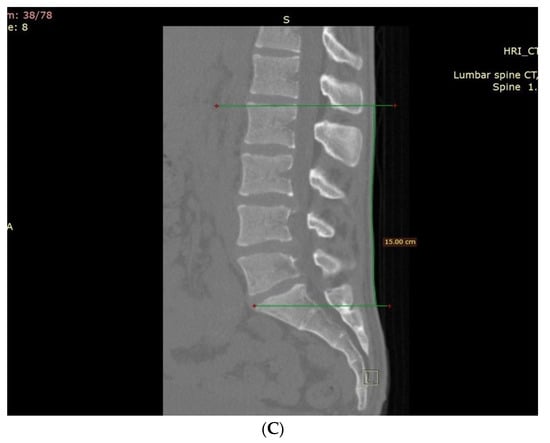

2. Methods